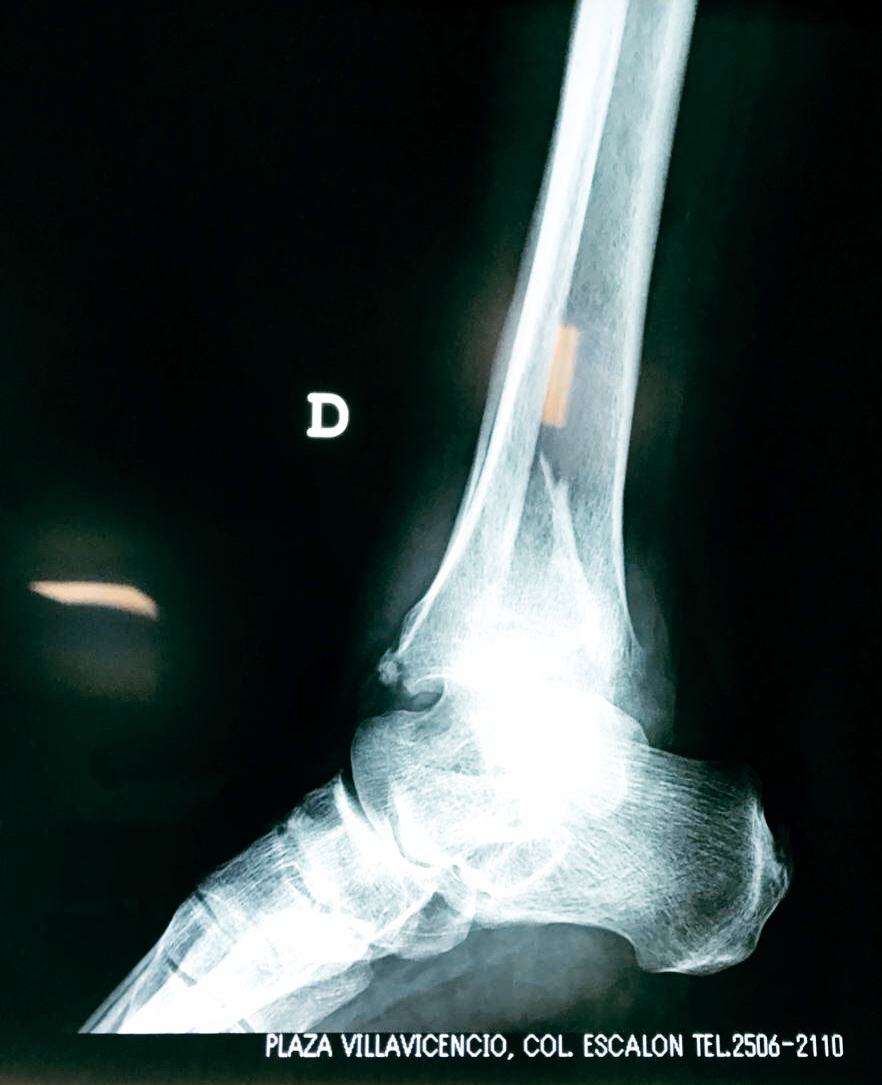

Una fractura de tobillo es la rotura de uno o más de los huesos del tobillo. Estas fracturas pueden ser:

- Parciales (el hueso está sólo parcialmente fisurado, no del todo).

- Completas (el hueso está perforado y está en 2 partes).

- Producirse en uno o ambos lados del tobillo.

Algunas fracturas de tobillo pueden requerir cirugía si:

- Los extremos de los huesos están desalineados entre sí (desplazados).

- La fractura se extiende hasta la articulación del tobillo (fractura intra-articular).

- Los tendones o ligamentos (tejidos que sujetan los músculos y los huesos entre sí) están rotos.

Cuando se necesita cirugía, es probable que esta implique el uso de clavijas de metal, tornillos o placas para sostener los huesos en su lugar mientras la fractura se consolida. Los elementos de soporte pueden ser temporales o permanentes.